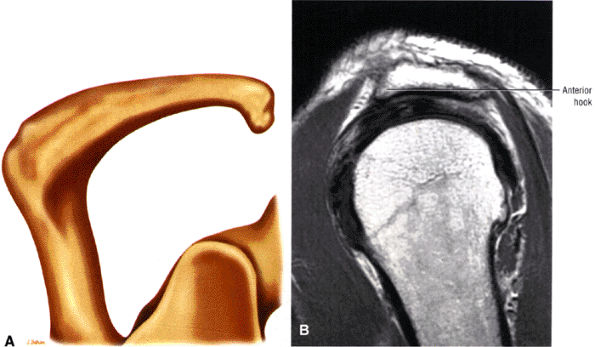

The acromion is classified into several types according to its morphology:

Type 1 (a flat or straight undersurface with a high angle of inclination)

Type 2 (a curved arc and decreased angle of inclination)

Type 3 (hooked anteriorly with a decreased angle of inclination)

Type 4 (upward convexity of the inferior surface) (see also the discussion of the etiology of shoulder impingement syndrome)